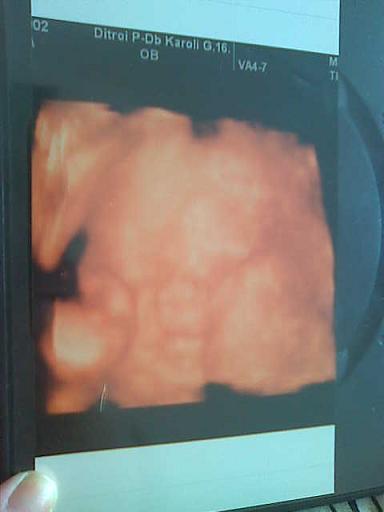

Nekem 4D-n mindent alaposan megnézett, azt mondta, átlagos a magzatvizem, szokásosan a méhlepény bal oldal mellső fali, minden rendben. Még leletet is kaptam!